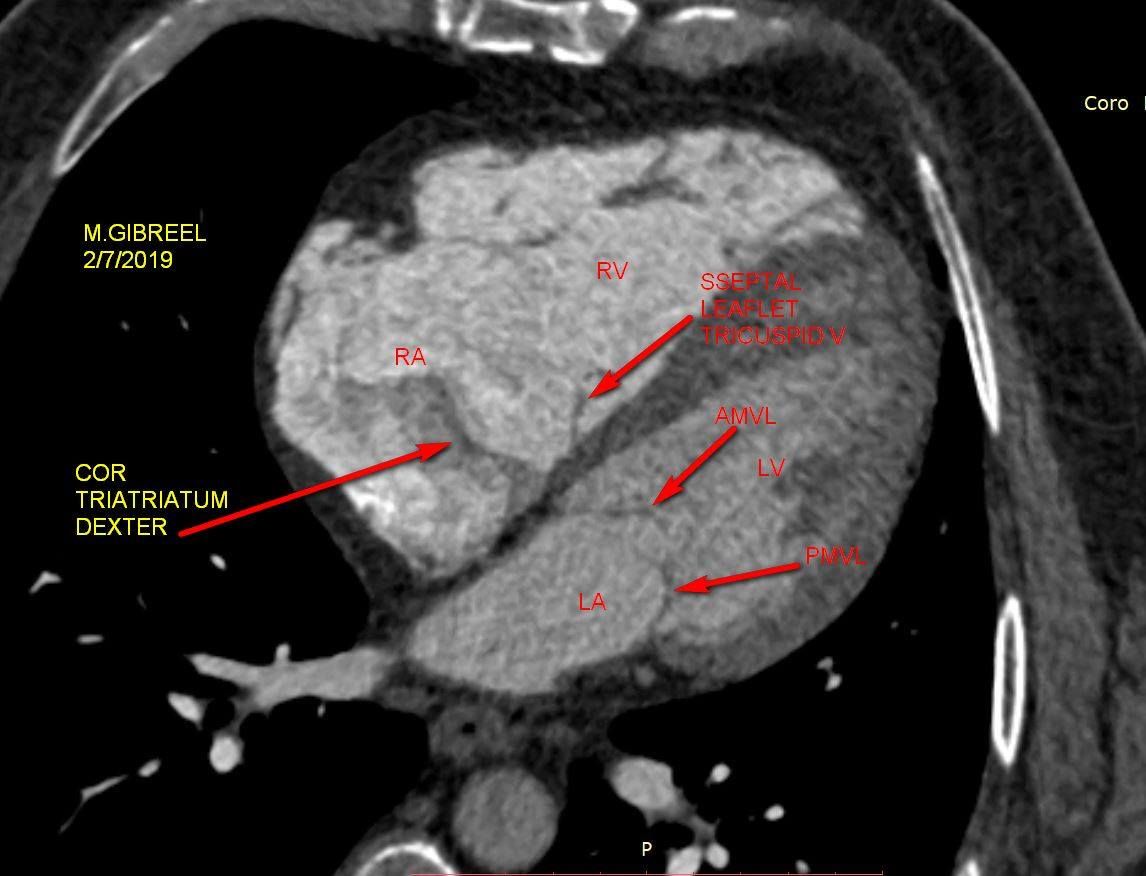

Cor triatriatum sinister & dexter

Cor Triatriatum Sinister

Mohamed Gibreel

, FEBR (Fellowship of Egyptian Board of Radiology ) Cardiac imaging consultant at Aswan heart center -Magdi Yacoub Foundation , Egypt